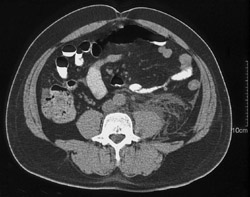

Stone Obstructing the Right Renal Pelvis